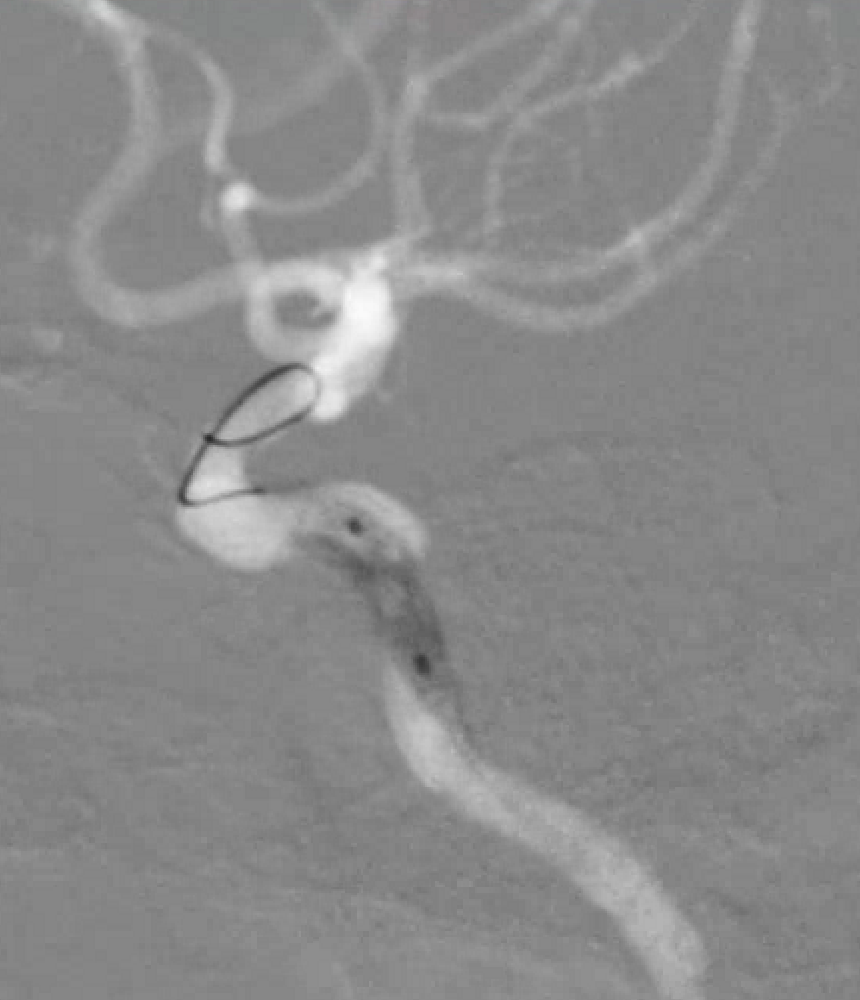

脑血管造影提示右侧颈内动脉颅内段多发动脉瘤(反主动脉弓)

脑血管造影提示右侧颈内动脉颅内段多发动脉瘤

4mm×30mm Streamline

术后4月余随访:多发动脉瘤均未见显影,远端残余轻度狭窄

术前术后对比